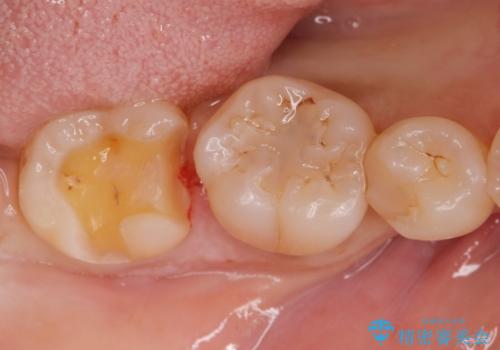

- 歯に食べ物が詰まるとの事で来院。

虫歯により歯が欠けていたので拡大鏡下で虫歯を除去した後、セラミックの詰め物で治療しました。

適合の良い詰め物が入りました。